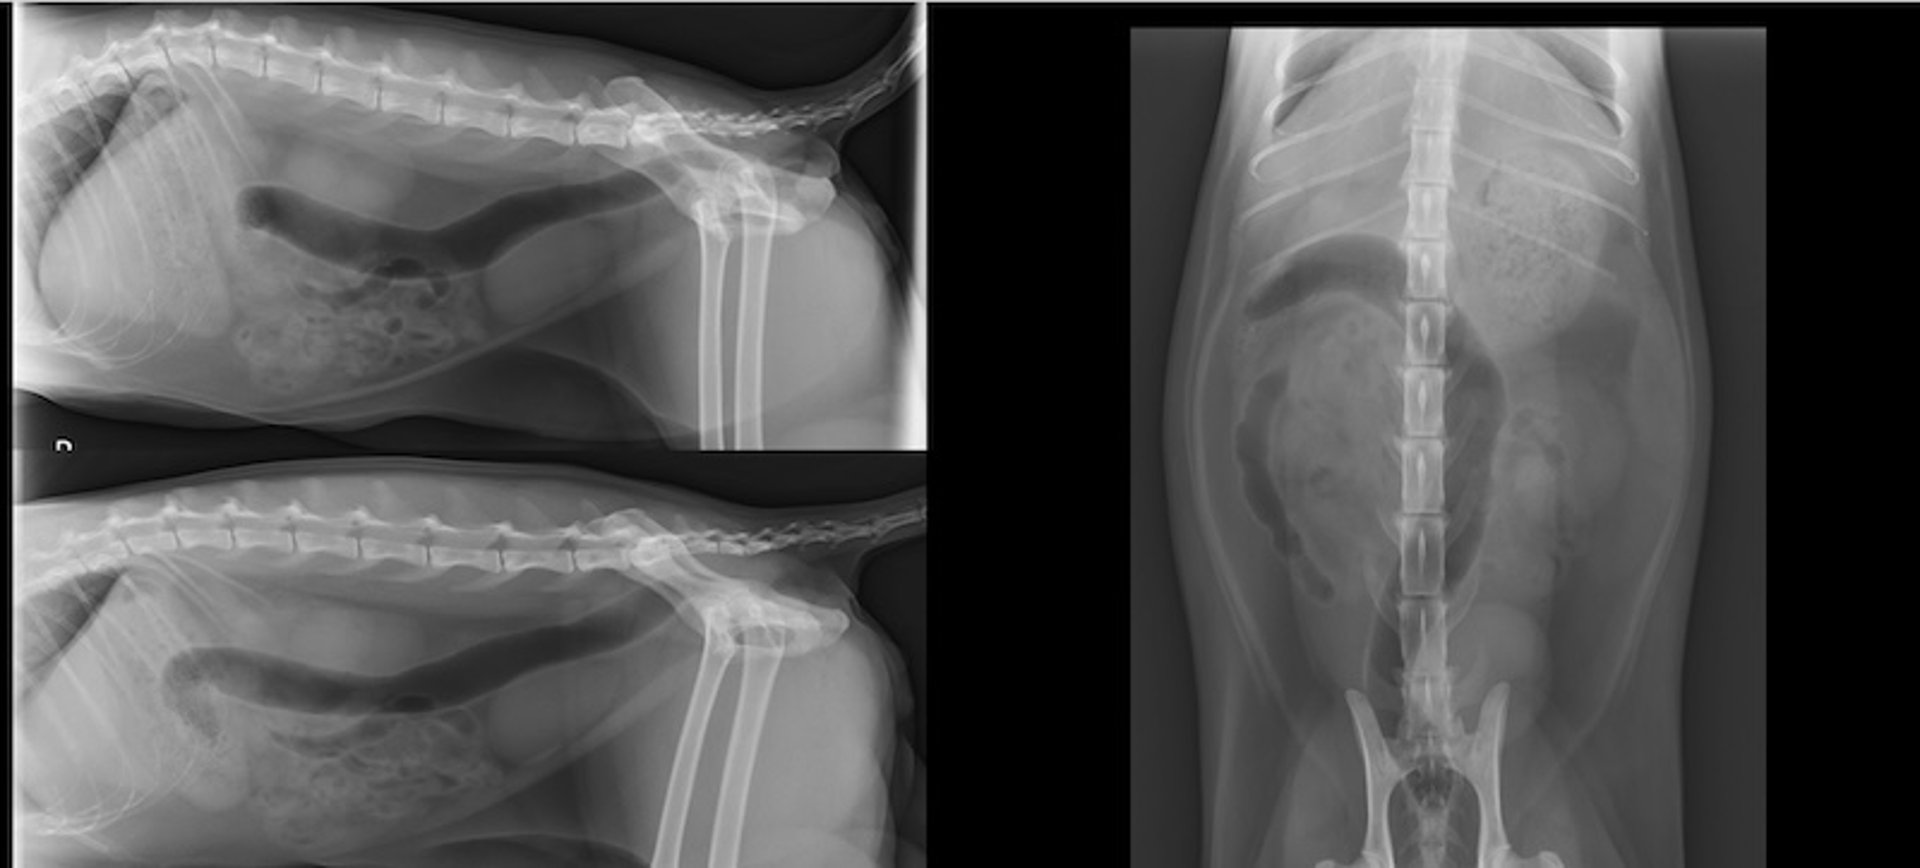

Radiografías en tres vistas, abdomen, gato

Radiografías de abdomen en 3 vistas bien posicionadas en un paciente felino: lateral derecha (arriba a la izquierda), lateral izquierda (abajo a la izquierda) y ventrodorsal (derecha).

Cortesía del Dr. Timothy Manzi.